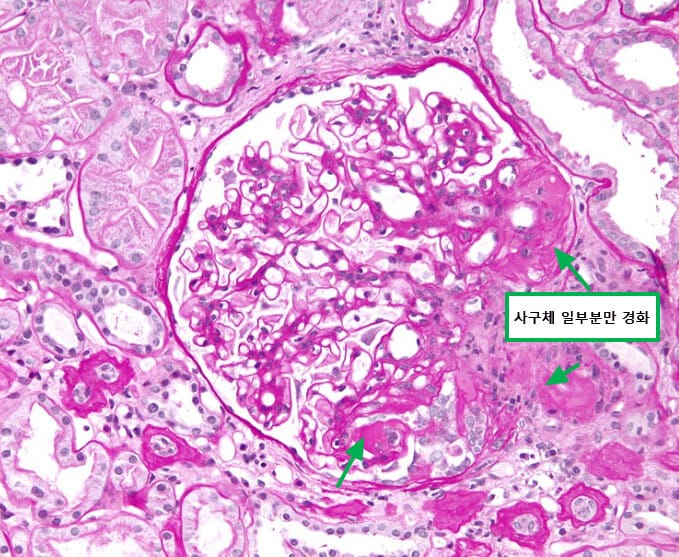

Focal Segmental Glomerulosclerosis (FSGS)

Focal Segmental Glomerulosclerosis (국소 분절성 사구체경화증)

Podocyte 손상 및 사구체 내압 증가로 일부 사구체가 국소적으로 경화됩니다.

FSGS는 일부 사구체(glomeruli)의 일부분(segmental)에서 경화(sclerosis)가 발생하는 질환으로, 성인 신증후군의 주요 원인 중 하나입니다. 병변은 국소적이지만 진행이 빠르고 치료에 대한 반응은 제한적입니다.

→ 일부 사구체(focal),에서, 일부 부위만(segmental) 경화 및 손상된 것이 특징입니다.

| 특징 요약 |

| 🟧 국소적, 분절성 경화 소견 |

| 🟧 스테로이드 반응이 낮고 재발률이 높음 |

| 🟧 점차 만성 신부전으로 진행할 수 있음 |